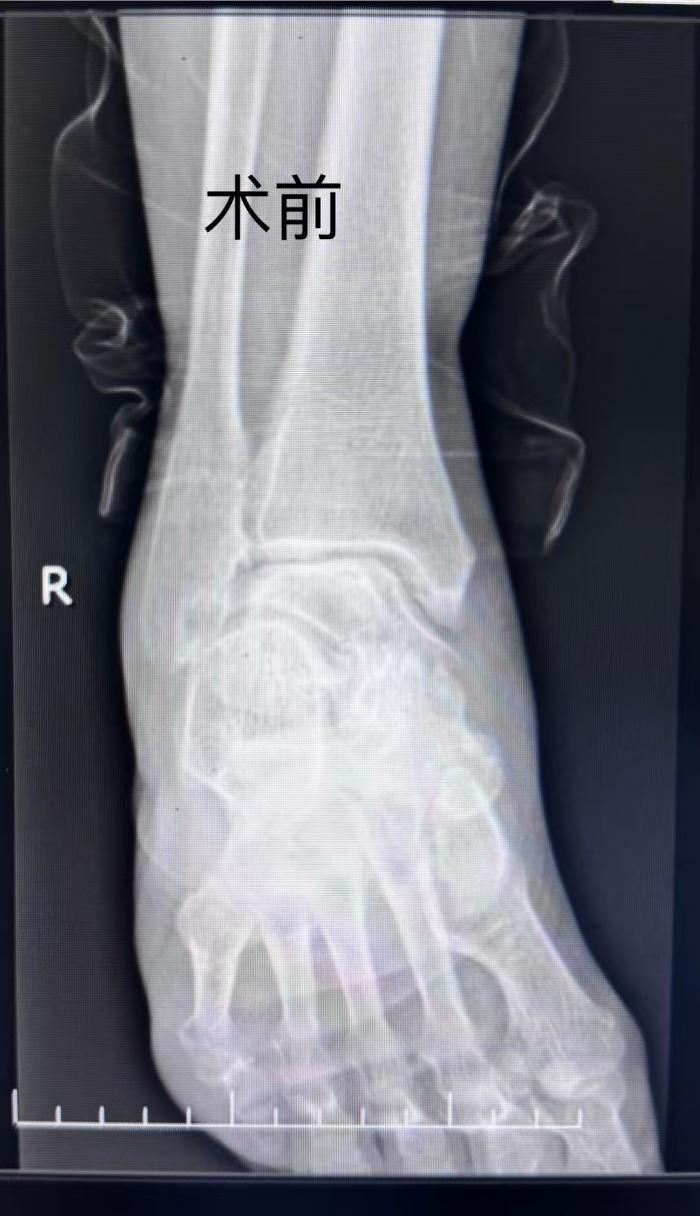

本网讯(通讯员 豆献梅)2025年5月12日,湘南学院附属医院骨一科成功为75岁的欧阳阿姨实施郴州市首例3D打印导板辅助下右踝关节置换术。这项融合数字化技术与精准外科理念的创新术式,让被踝关节病痛折磨十余年的患者,术后5天即实现助行器辅助下地行走,重新拥抱生活的希望。

此次就诊的契机,源于欧阳阿姨的老伴因不慎摔伤导致股骨颈骨折,在湘南学院附属医院住院治疗。欧阳阿姨在病房照顾期间,骨一科主任唐新文注意到她走路一瘸一拐,询问情况并进行查体后,立即安排了右踝关节DR检查,最终以“右踝关节骨关节炎”将其收入科室治疗。

![]()

唐新文主任团队接诊后,进行了系统评估。影像学显示,胫距关节面严重磨损,踝关节活动度<15°(正常背屈 20/跖屈 50°),且踝关节力线异常。考虑到患者需照料术后配偶的特殊需求,团队决定采用3D 打印导板技术联合第三代解剖型假体系统,实施全踝关节置换术,在解除病痛的同时最大限度保留关节功能。主管医生吕晨与家属详细讲解了手术治疗方案及术后康复方案,消除了家属的顾虑。欧阳阿姨也坚定地表示:“我的老伴两次摔跤,两次手术都是在唐主任这里做的,所以我绝对相信你们的医疗水平。”